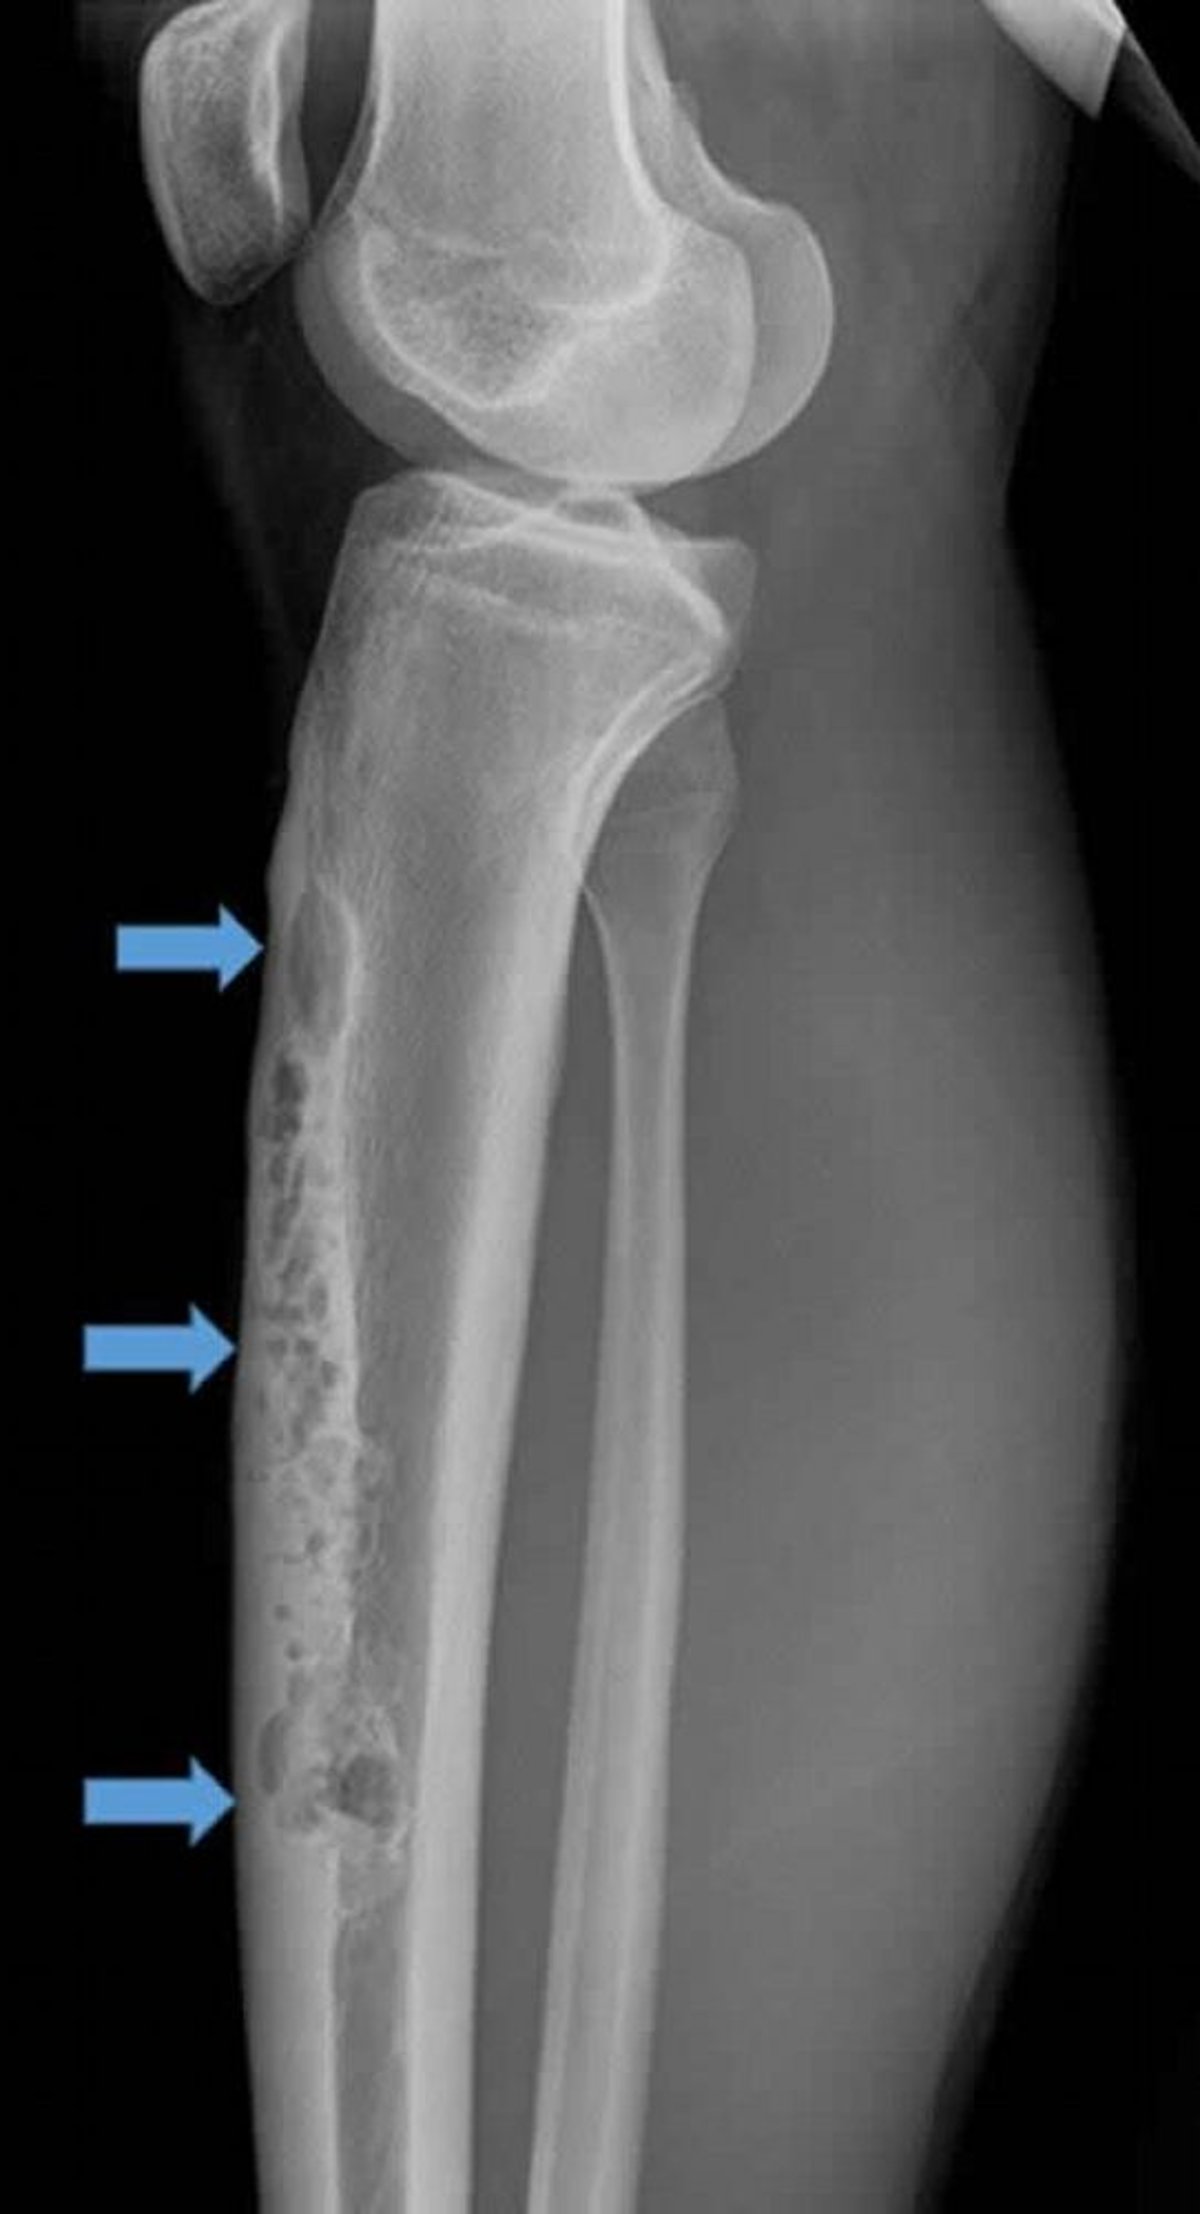

Diese laterale Röntgenaufnahme der rechten Tibia zeigt ein großes anteriores intracorticales Adamantinom (Pfeile). Beachten Sie das durchlässige, osteolytische „Seifenblasen“-Aussehen.

Image courtesy of Michael J. Joyce, MD, and Hakan Ilaslan, MD.